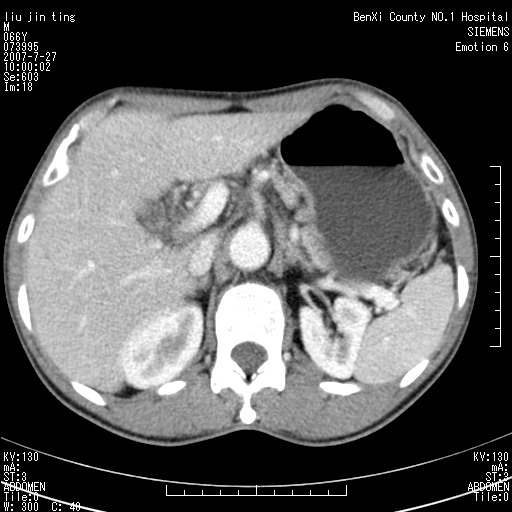

肠系膜根部肿块,累及肠系膜上动脉,考虑肿大淋巴结累及肠系膜上动脉.

腹腔干至肠系膜上动脉水平肿大淋巴结影可能性大.

钩突是正常的,只见腹膜后淋巴结的肿大,考虑淋巴瘤或转移可能。

腹膜后占位性病变,首先考虑肿大淋巴结。

后腹膜肿块,包围血管,考虑淋巴恶性病变,淋巴瘤或转移。